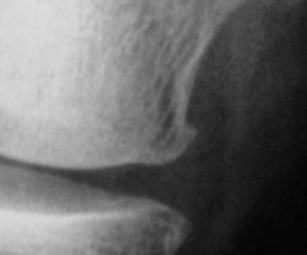

Основным симптомом болезни Пеллегрини — Штиды является боль, которая всегда соответствует месту расположения оссификата, может распространяться по ходу запирательного нерва или поднадколенниковой ветви подкожного нерва на переднюю поверхность голени. У 1/3 больных боли усиливаются в ночное время и носят жгучий сверлящий характер. Кроме того, отмечают ограничение движений в коленном суставе, как сгибания, так и разгибания, которые обычно сочетаются с отеком мягких тканей коленного сустава, местной гипертермией, гиперестезией или гипостезией в зоне отека, а также атрофией мышц бедра и голени. В раннем периоде после травмы, когда клиническая картина идентична ушибу или дисторсии коленного сустава, а также при сочетании с внутренними повреждениями его диагностика затруднена. Через 3—4 недели после травмы на рентгенограммах коленного сустава определяют оссификат (рис.), имеющий вид скобки, серпа или неправильную форму, который отделен от надмыщелка бедренной кости полоской просветления. При отрицательных рентгенологических данных, но при наличии пальпируемого оссификата необходимо произвести рентгеновские снимки с внутренней или наружной ротацией конечности на 20° для устранения наслоения оссификата на контур мыщелка бедра. Информацию о степени зрелости оссификата может дать радионуклидное исследование. Дифференциальный диагноз проводят с отрывным переломом медиального надмыщелка бедренной кости, который выявляется на рентгенограмме сразу после травмы. Кроме того, краевой дефект надмыщелка по форме и размерам соответствует оторванному фрагменту кости. Похожую рентгенологическую картину можно наблюдать при перестроенном процессе в надмыщелке тракционного генеза, возникающем в результате многократных форсированных напряжений большой приводящей мышцы бедра, например у футболистов. Однако постепенное развитие этого заболевания, более молодой возраст, связь с занятиями спортом помогают уточнить диагноз.

В раннем периоде после травмы, когда клиническая картина идентична ушибу или дисторсии коленного сустава, а также при сочетании с внутренними повреждениями его диагностика затруднена. Через 3—4 недели после травмы на рентгенограммах коленного сустава определяют оссификат (рис.), имеющий вид скобки, серпа или неправильную форму, который отделен от надмыщелка бедренной кости полоской просветления. При отрицательных рентгенологических данных, но при наличии пальпируемого оссификата необходимо произвести рентгеновские снимки с внутренней или наружной ротацией конечности на 20° для устранения наслоения оссификата на контур мыщелка бедра. Информацию о степени зрелости оссификата может дать радионуклидное исследование. Дифференциальный диагноз проводят с отрывным переломом медиального надмыщелка бедренной кости, который выявляется на рентгенограмме сразу после травмы. Кроме того, краевой дефект надмыщелка по форме и размерам соответствует оторванному фрагменту кости. Похожую рентгенологическую картину можно наблюдать при перестроенном процессе в надмыщелке тракционного генеза, возникающем в результате многократных форсированных напряжений большой приводящей мышцы бедра, например у футболистов. Однако постепенное развитие этого заболевания, более молодой возраст, связь с занятиями спортом помогают уточнить диагноз.

Решил выставить данное изображение лишь с той целью, что данное заболевание (синдром) не встречал в своей своей практике уже весьма давно.